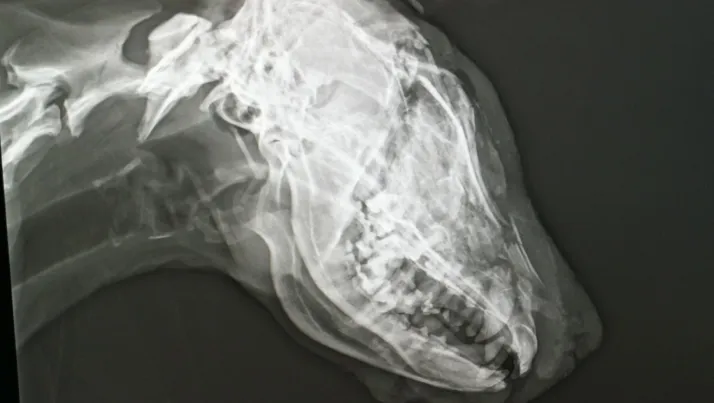

Tras rescatar al animal de la cuneta, las voluntarias de Defensa Animal Zamora llevaron a la perra a urgencias veterinarias, donde "fue imposible" salvarle la vida "dado que le habían partido el cráneo antes de atarla a la bola del vehículo".